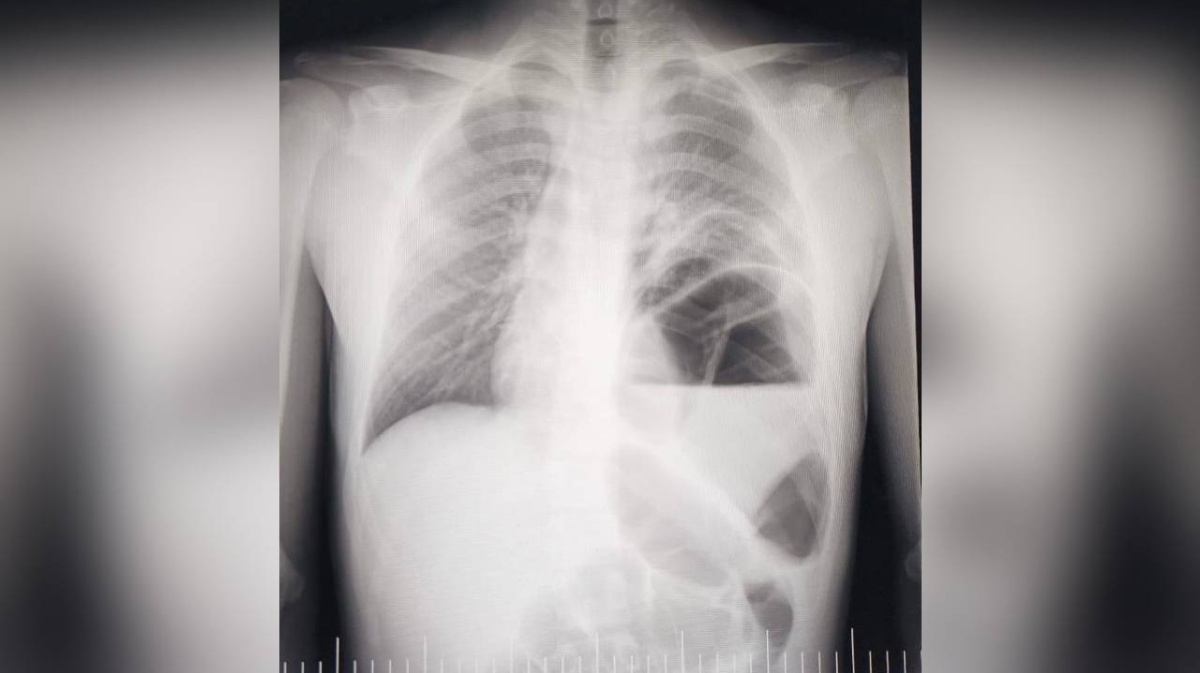

Врачи детской клинической больницы №2 в Воронеже прооперировали двух пациентов с одним редким пороком развития.  Он называется диафрагмальной грыжей, пояснили в больнице в субботу, 4 февраля.

Органы переместились из брюшной полости в грудную клетку. Во время операции установили, что сместились желудок, селезёнка, поперечная ободочная кишка, сальник и участок тонкого кишечника.